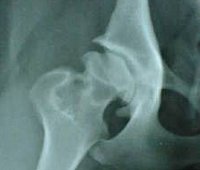

Артропластика тазобедренного сустава

Артропластика тазобедренного сустава. Хирургическое вмешательство, при котором создаются условия, предотвращающие образование анкилоза (состояние, при котором сустав становится неподвижным), или подвижность анкилозирующего сустава восстанавливается. Это произведено с явными изменениями в суставных поверхностях из-за необработанного врожденного вывиха бедра, серьезного деформирующего артроза и других патологий. Он включает разделение головки бедренной кости и вертлужной впадины, моделирование этих анатомических структур с созданием конгруэнтных поверхностей, размещение гомотрансплантата или области фасции пациента между структурами, образующими сустав.

Показания к хирургическому вмешательству включают деформирующий остеоартроз с серьезным ограничением подвижности и нарушением функции конечностей, нелеченным врожденным вывихом бедра, рядом других заболеваний и патологических состояний (в том числе последствия травматических повреждений), сопровождающихся анкилозом или анкилозом. Способ не применяется при инфекционных поражениях соседних суставов и мягких тканей, нарушениях системы свертывания крови, острых инфекциях, острых соматических заболеваниях в острой стадии.